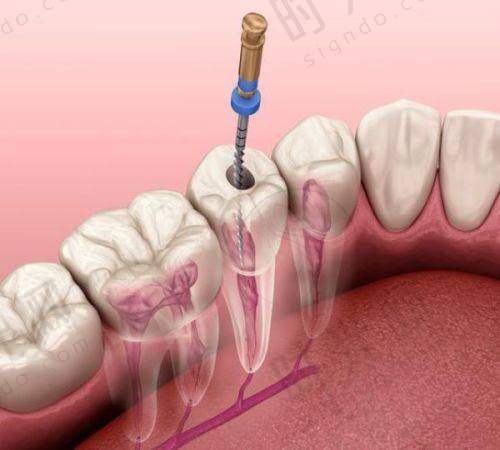

2. 根管治疗:“救牙髓”的关键,针对“牙神经发炎”导致的松动

如果牙齿松动同时伴有剧烈疼痛(尤其是晚上疼得睡不着)、牙龈起脓包,可能不是牙周病,而是牙髓感染(俗称“牙神经发炎”)。牙髓感染会导致牙根尖周围组织发炎、化脓,就像牙根周围“长了个小脓包”,把牙齿“顶”得松动。这种情况必须做根管治疗:清除感染的牙髓,用药物消毒根管,再填充起来,消除炎症后牙齿自然会稳固。

适合人群:因蛀牙、牙齿外伤导致牙髓感染的松动牙,尤其是“咬东西就疼,不咬不疼”的情况。比如38岁的陈女士,蛀牙没及时补,发展到牙髓炎,大牙松动还流脓,做根管治疗后,炎症消退,牙齿松动明显减轻,现在已经能正常吃饭了。注意:根管治疗后的牙齿会变“脆”,建议做个牙冠保护,避免咬硬物时劈裂。